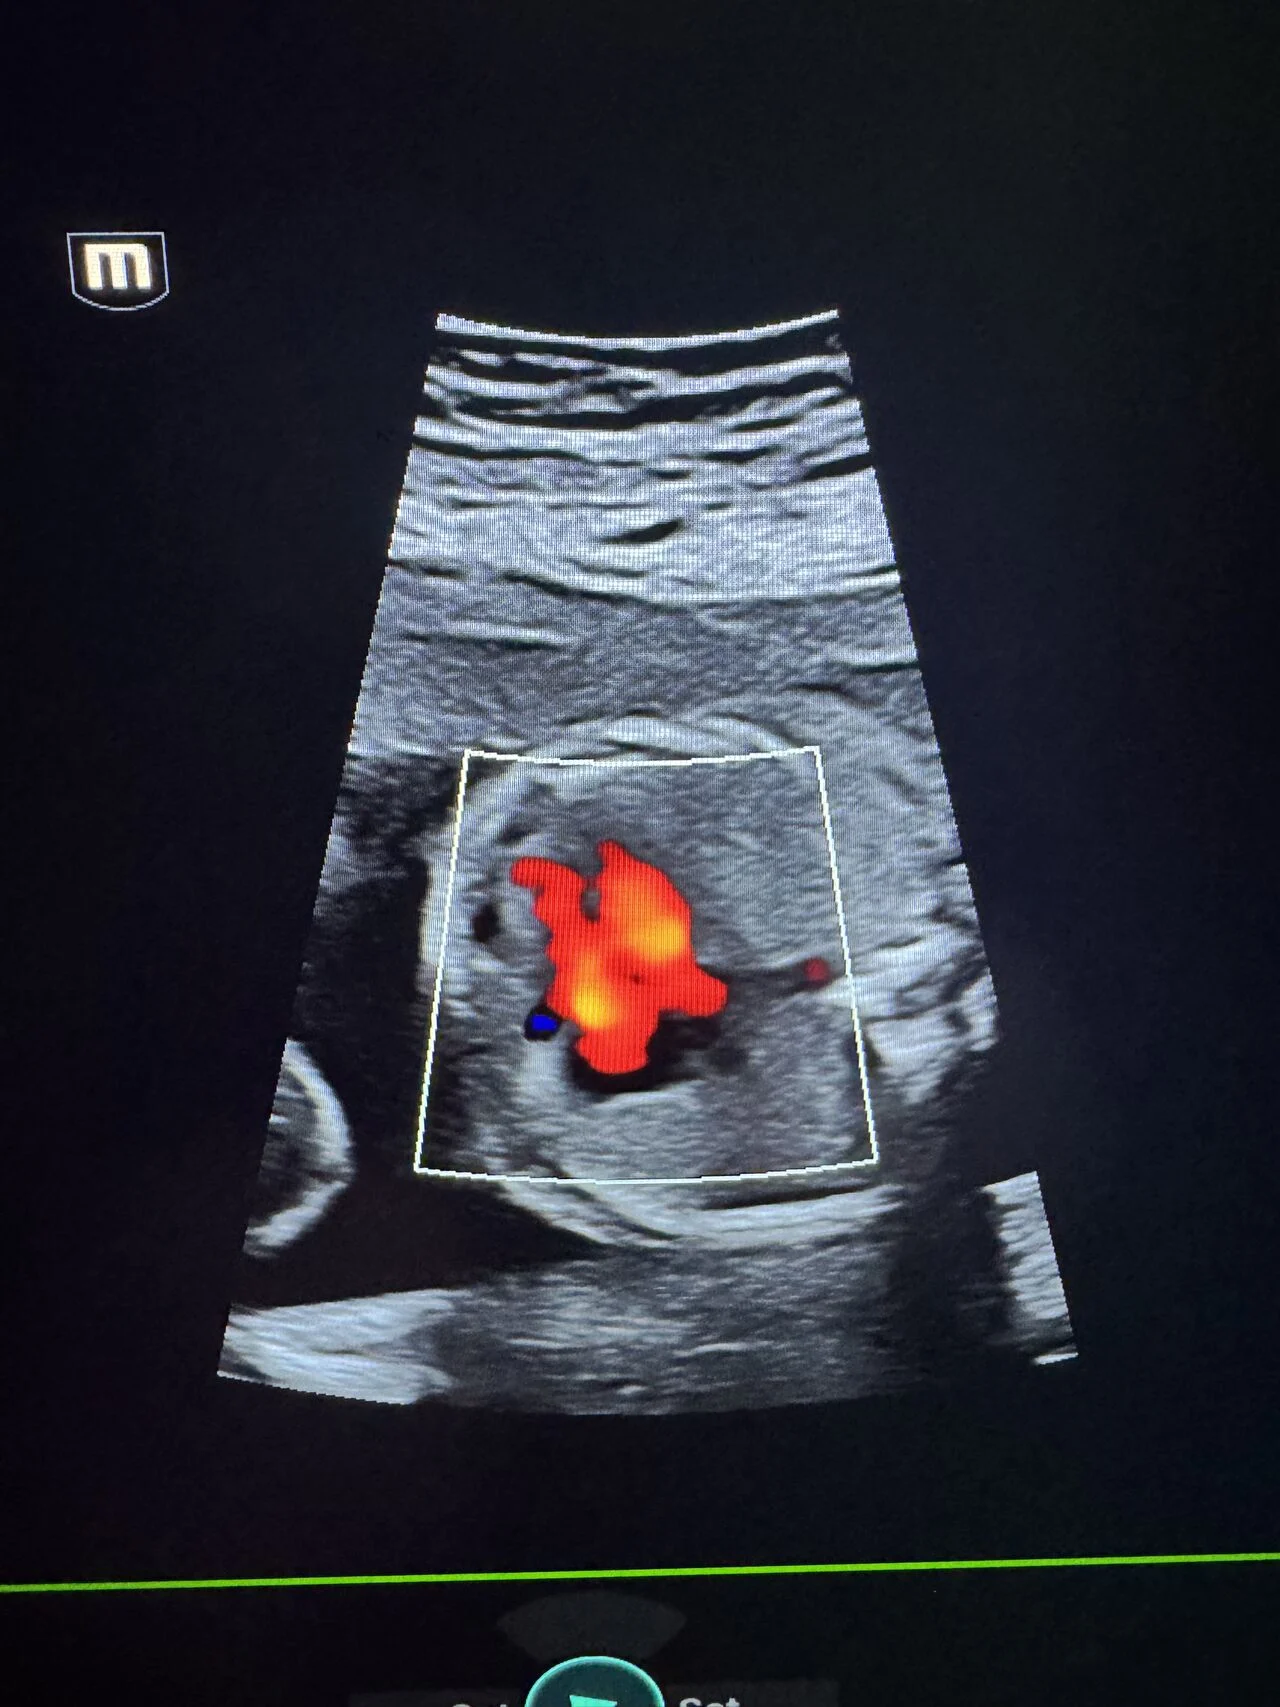

“Fetal Anomaly Case | Semilobar Holoprosencephaly

A prenatal ultrasound case demonstrating features of semilobar holoprosencephaly.

An associated ventricular septal defect (VSD) was also identified.